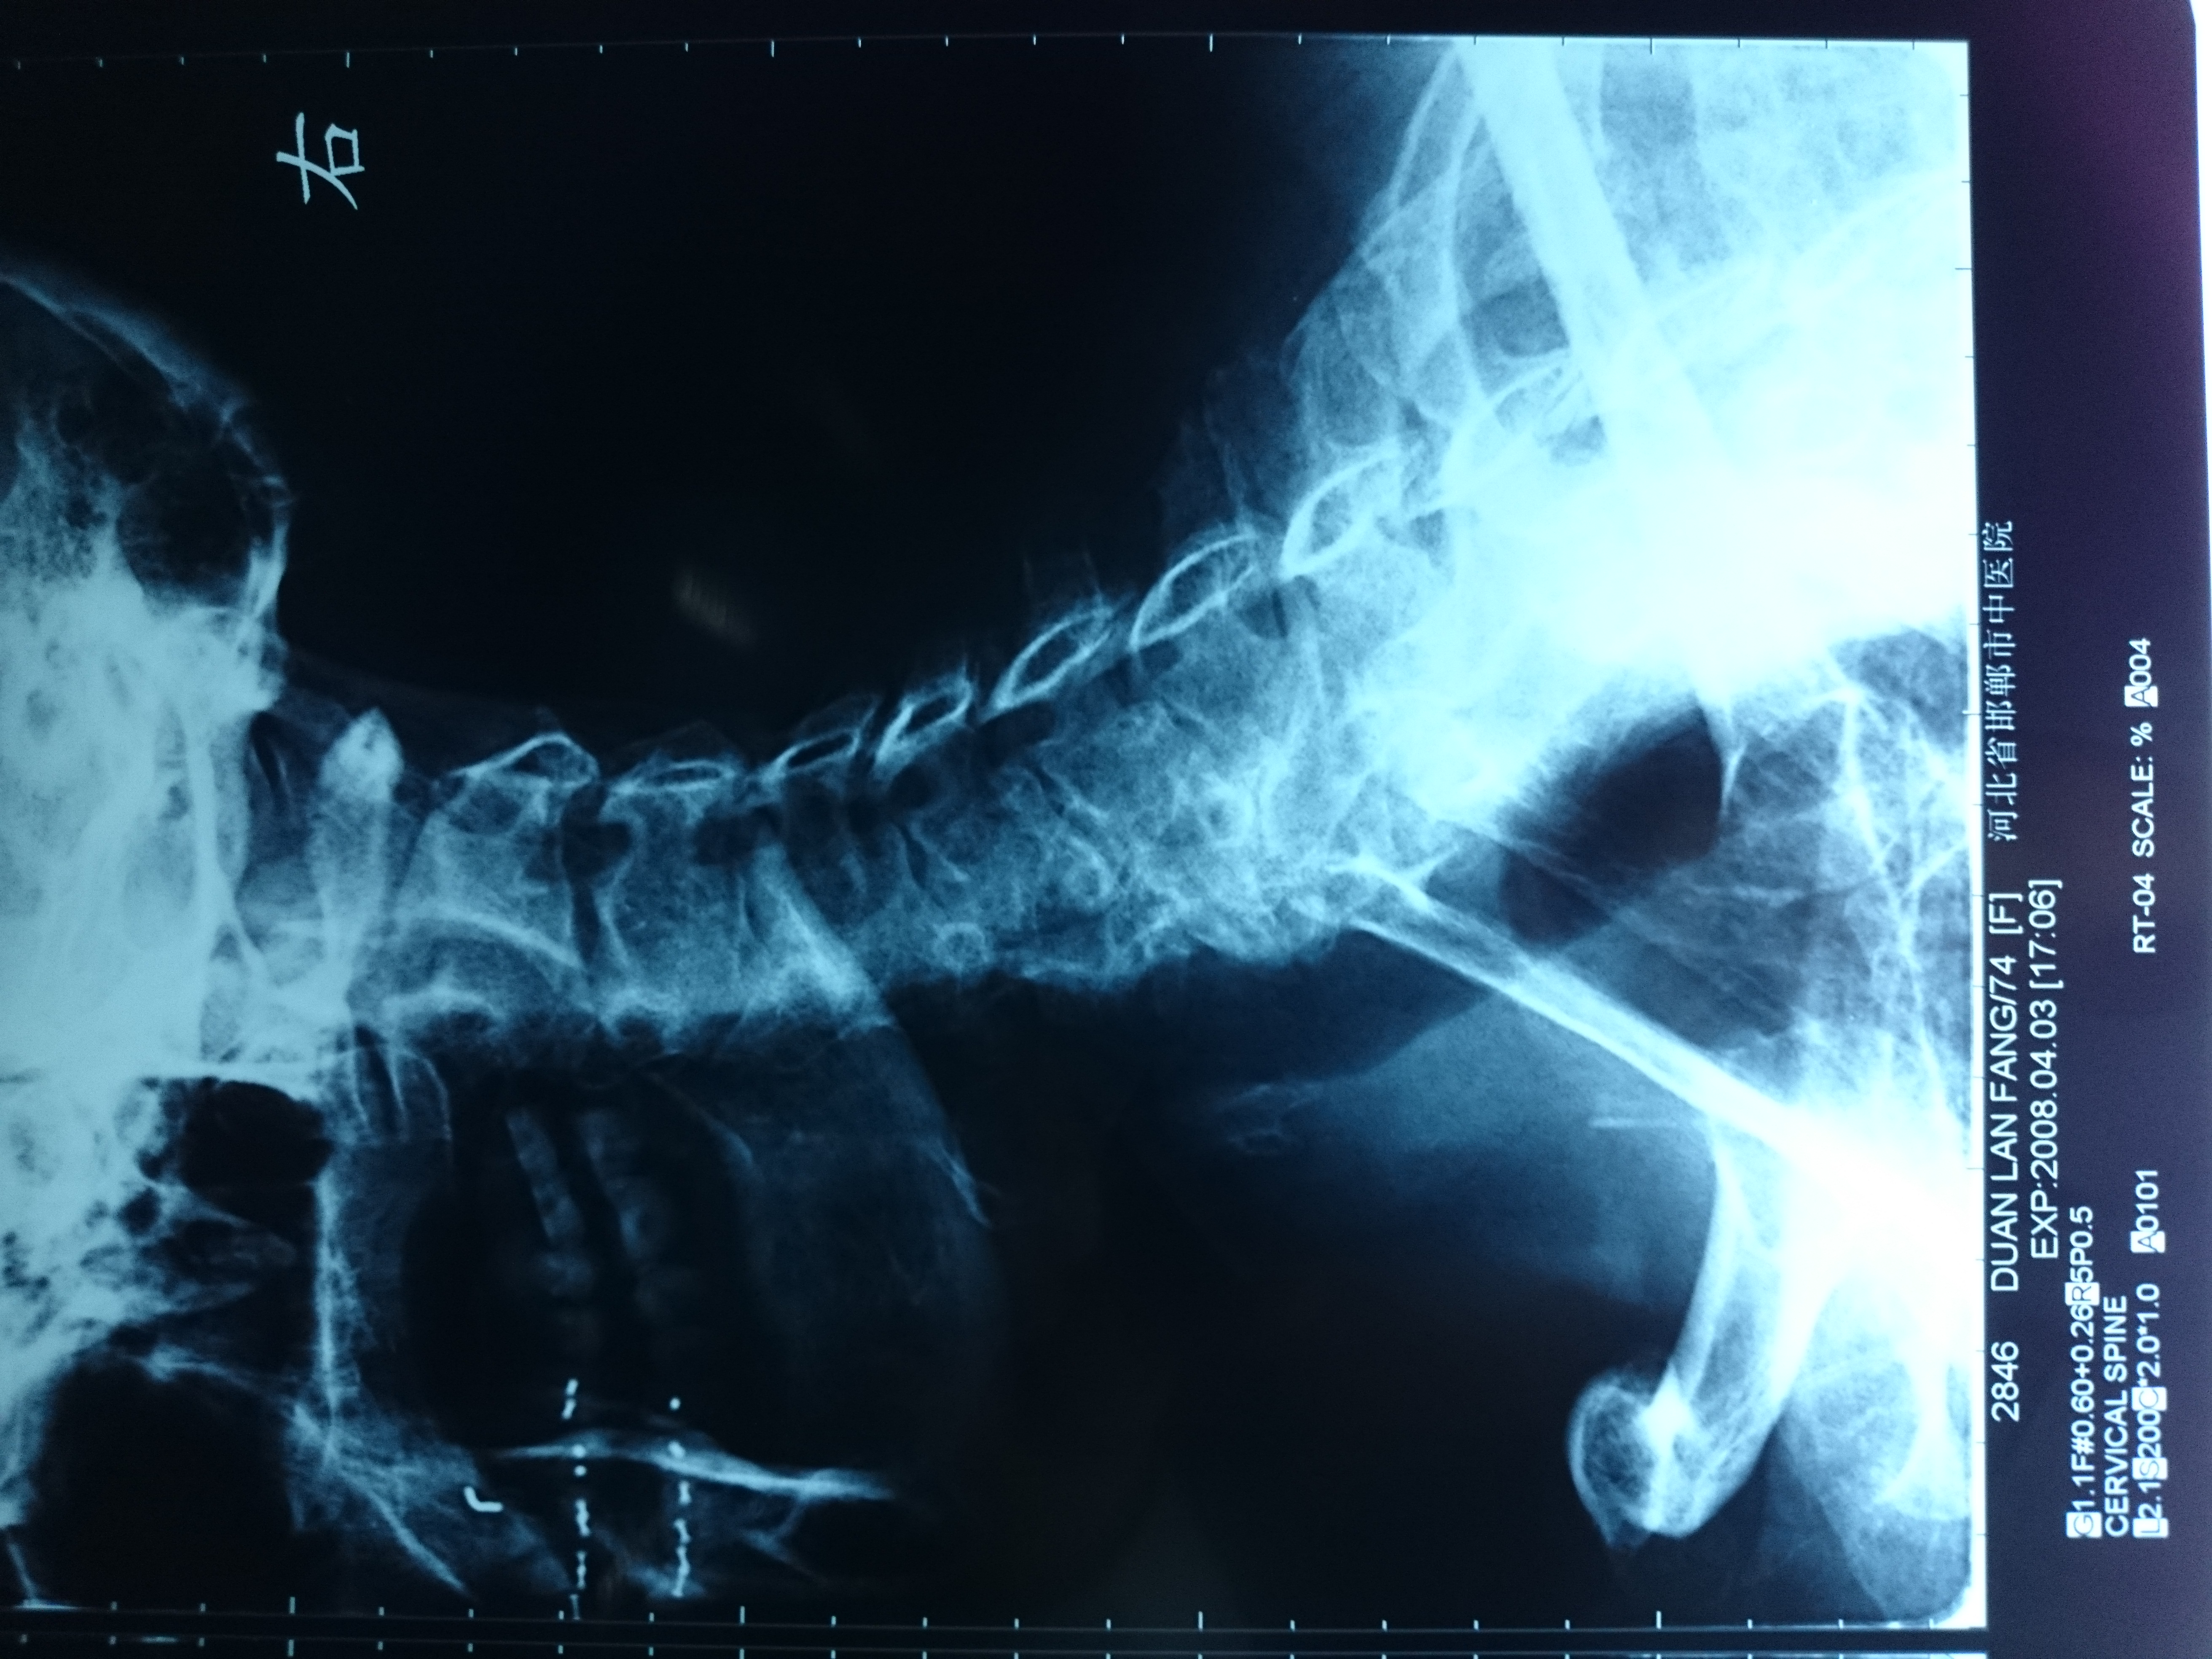

首页 > 张恒云工作室 > 影像资料 十四